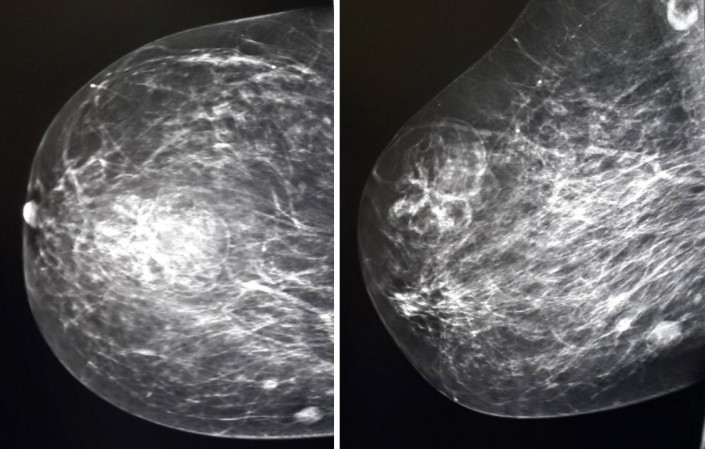

( A ) Polythelia нештатный сосок ниже подгрудной складки. ( B ) Полимастия при выраженной гипоплазии левой грудной клетки, сколиозе и деформации Шпренгеля. ( C ) Иссечение сосково-ареолярного комплекса добавочной груди. ( D ) Добавочная ткань молочной железы сохранена и мобилизована на задней ножке. ( E ) Добавочная ткань молочной железы транспонируется сверху и фиксируется на грудной клетке для улучшения поддержки остаточной груди. ( F ) Результат после транспозиции верхней части груди книзу и медиально на верхнелатеральной ножке, остаточный рубец расположен в подгрудной складке.

( B ) Полимастия при выраженной гипоплазии левой грудной клетки, сколиозе и деформации Шпренгеля. ( C ) Иссечение сосково-ареолярного комплекса добавочной груди. ( D ) Добавочная ткань молочной железы сохранена и мобилизована на задней ножке. ( E ) Добавочная ткань молочной железы транспонируется сверху и фиксируется на грудной клетке для улучшения поддержки остаточной груди. ( F ) Результат после транспозиции верхней части груди книзу и медиально на верхнелатеральной ножке, остаточный рубец расположен в подгрудной складке.